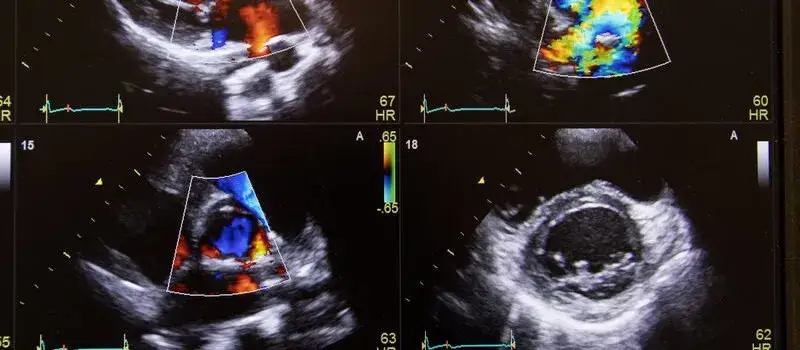

USG Dopplera to badanie ultrasonograficzne, które wykorzystuje efekt Dopplera do oceny szybkości i kierunku przepływu krwi. Podczas badania, fale dźwiękowe są wysyłane w kierunku krwi płynącej w naczyniach, a zmiana ich częstotliwości pozwala na określenie prędkości i kierunku przepływu. Proces ten jest bezpieczny i nieinwazyjny, co czyni go popularnym narzędziem diagnostycznym w wielu placówkach medycznych.

W trakcie badania pacjent leży na kozetce, a lekarz nakłada na skórę żel, który ułatwia przewodzenie fal ultradźwiękowych. Na monitorze pojawia się obraz, który ilustruje przepływ krwi przez naczynia. Po zakończeniu badania lekarz analizuje uzyskane wyniki i interpretuje je w kontekście stanu zdrowia pacjenta. To właśnie ta interpretacja jest kluczowa dla zrozumienia, co oznaczają wyniki badania i jakie kroki należy podjąć w celu poprawy zdrowia.